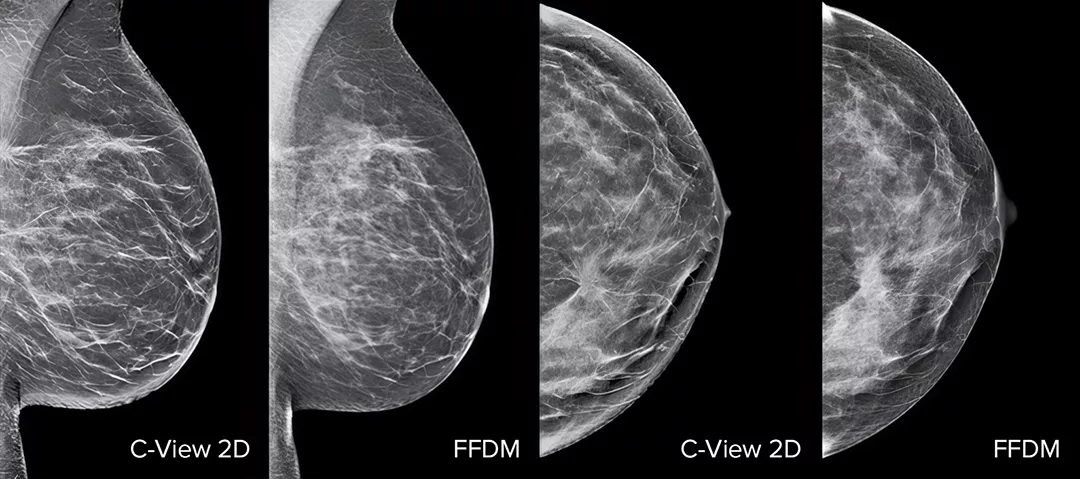

Il software C-View e le immagini sintetiche 2D generate istantaneamente migliorano le prestazioni dello screening per i tumori della mammella1-4. I dettagli sono più precisi, le analisi più veloci e la dose di radiazione ridotta. Le immagini 2D C-View sono clinicamente validate3,5 e approvate dalla FDA per sostituire a livello diagnostico le immagini FFDM nell'ambito dell'esame di screening tramite tomosintesi.

Distorsioni architetturali, masse e foci generalmente presenti nelle microcalcificazioni sono meglio visibili nell’immagine 2D C-View™ rispetto all'immagine 2D FFDM tradizionale o alle sezioni di tomosintesi.4,6-9

La prova è nei dettagli

Le immagini 2D C-View sono clinicamente validate3,5 e approvate dalla FDA per sostituire a livello diagnostico le immagini FFDM nell'ambito dell'esame di screening tramite tomosintesi. Possono essere utilizzate come supporto per analizzare le sezioni di tomosintesi. Studi pubblicati dimostrano che l'esame di mammografia 3D a bassa dose individua i tumori invasivi in anticipo, riducendo allo stesso tempo anche il numero di richiami per falsi positivi rispetto al solo esame 2D.4,5,7

Distorsioni architetturali, masse e foci generalmente presenti nelle microcalcificazioni sono meglio visibili nell'immagine 2D C-View™ rispetto all'immagine 2D FFDM tradizionale o alle sezioni di tomosintesi.4,6-9